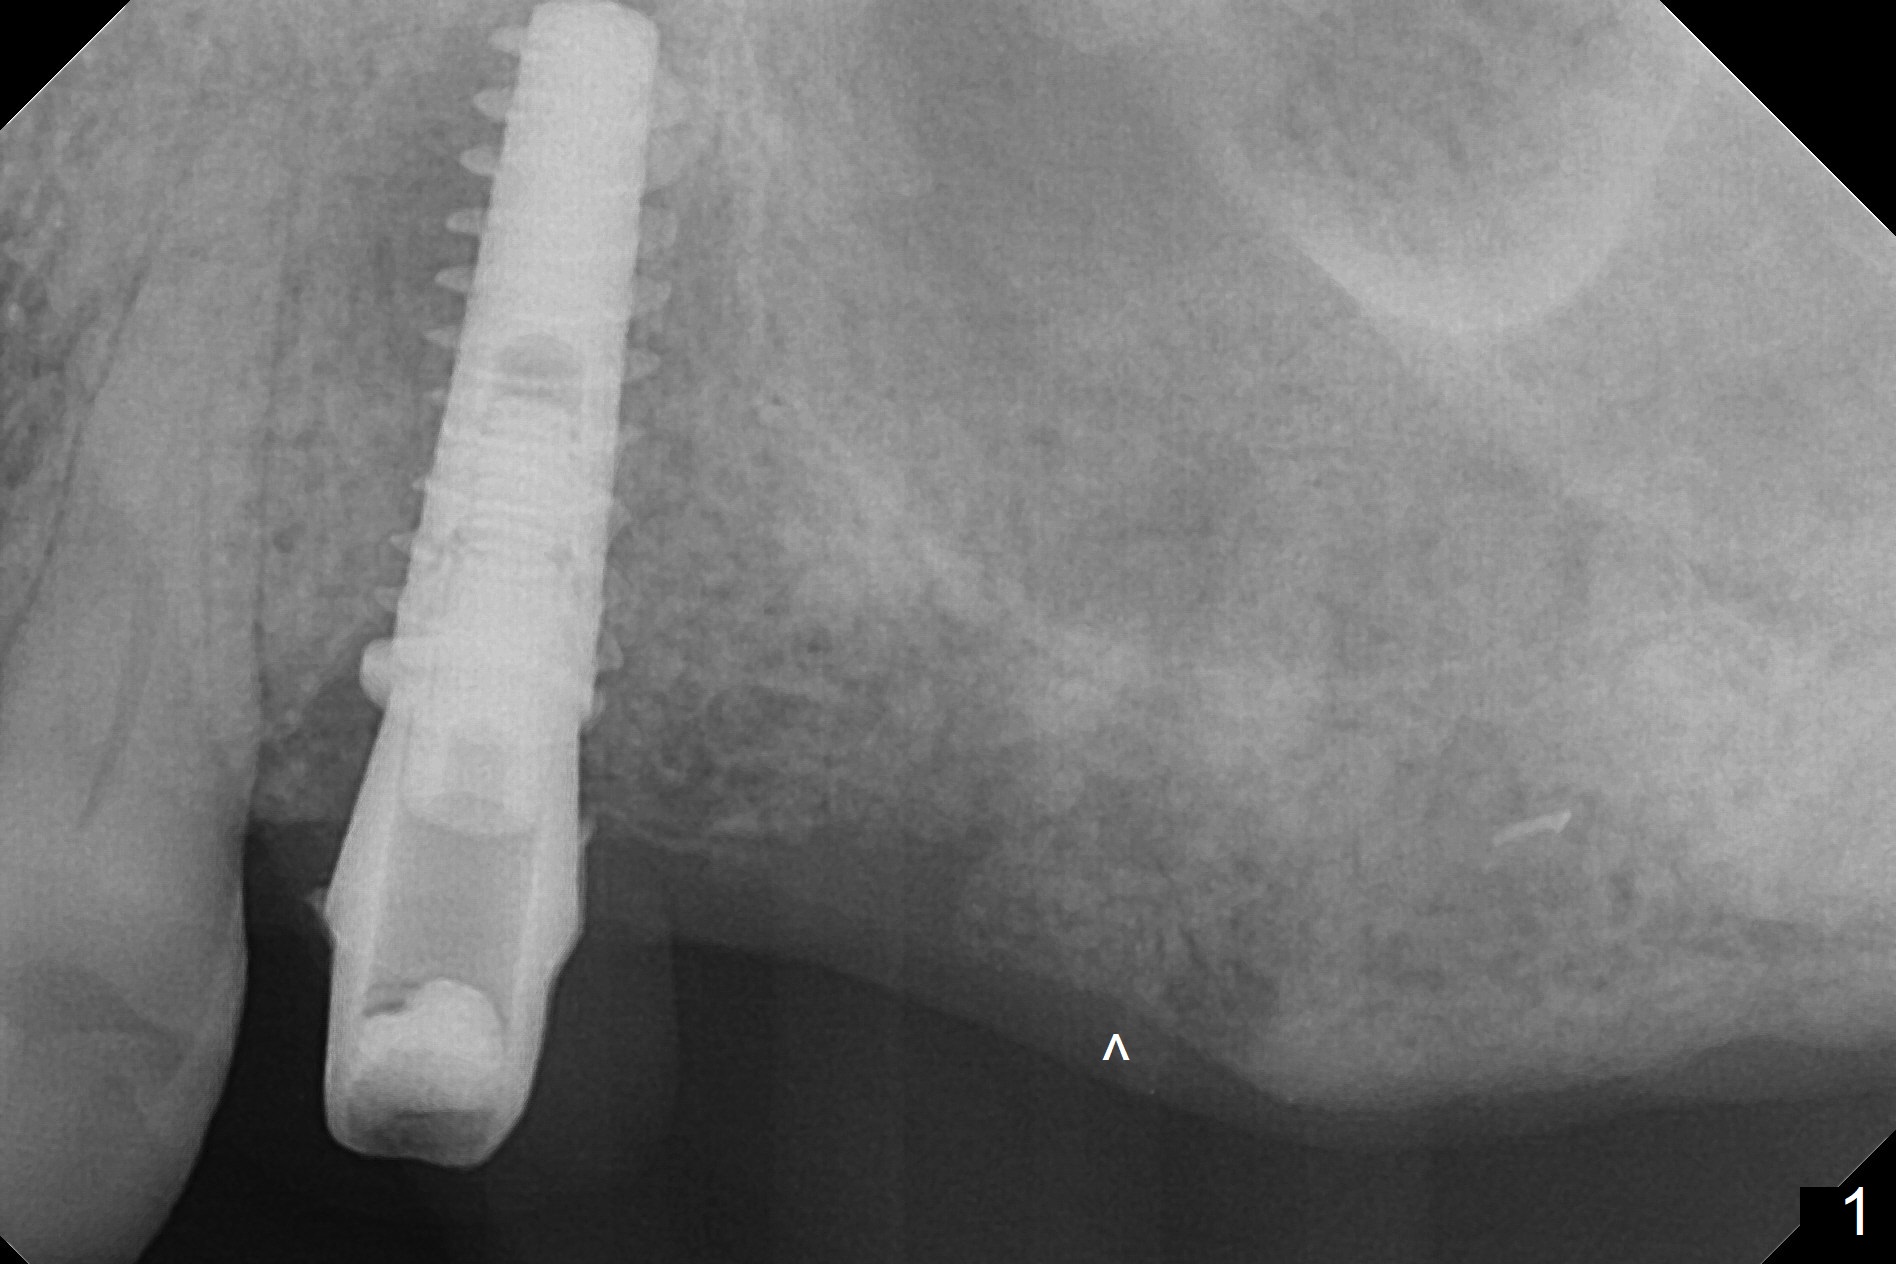

A 73-year-old man lost #15 implant 4 months ago with socket preservation (Fig.1 (taken 1 month post bone graft (^)). The tooth #14 was extracted with socket preservation ~ 9 months ago. The sites should be not so dense that Magic Split will be used to start osteotomy for 7 mm (Fig.2). Prior to this step, use 1.5 mm or starter drill and surgical stent to mark the initial osteotomy. BEB is followed by Magic Expanders (1 mm longer each). Implants are expected to be 9 or 11 mm long (Fig.3,4).